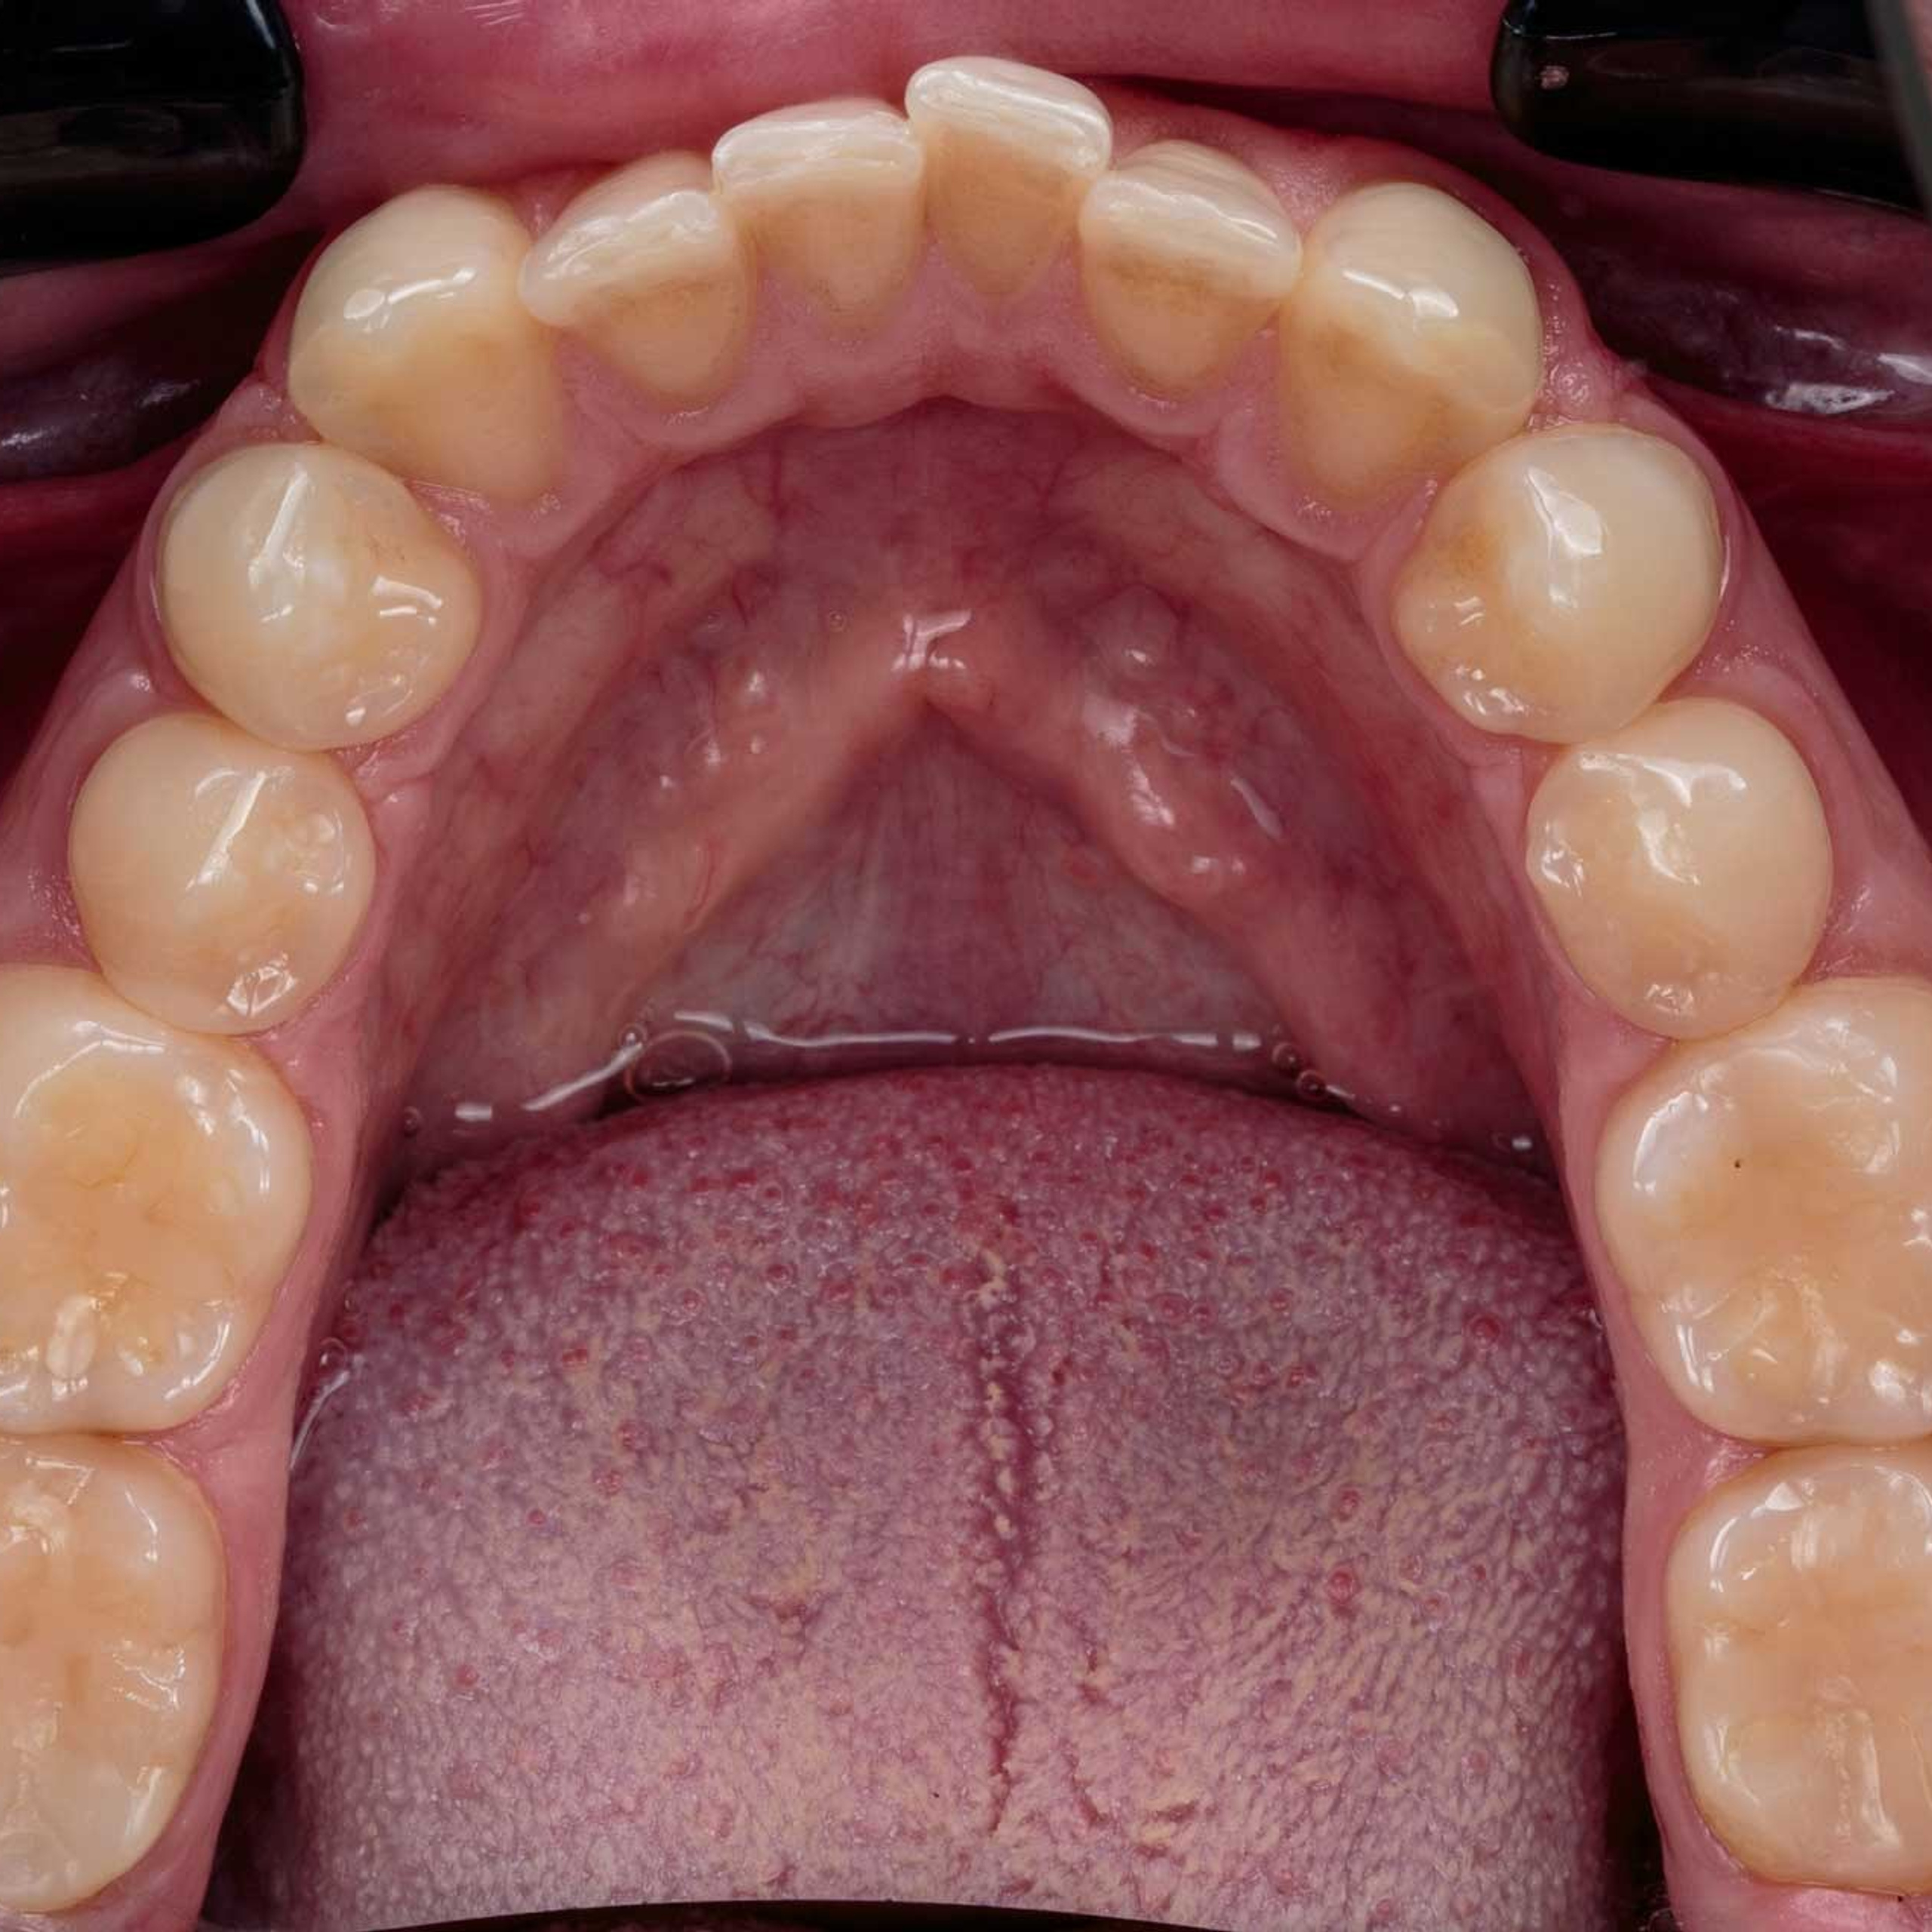

Фотографии учеников до обучения

Фотографии после обучения